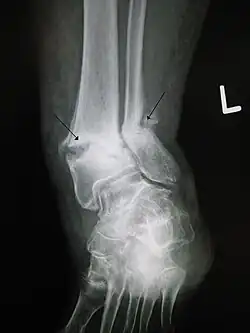

Open ankle fracture with luxation